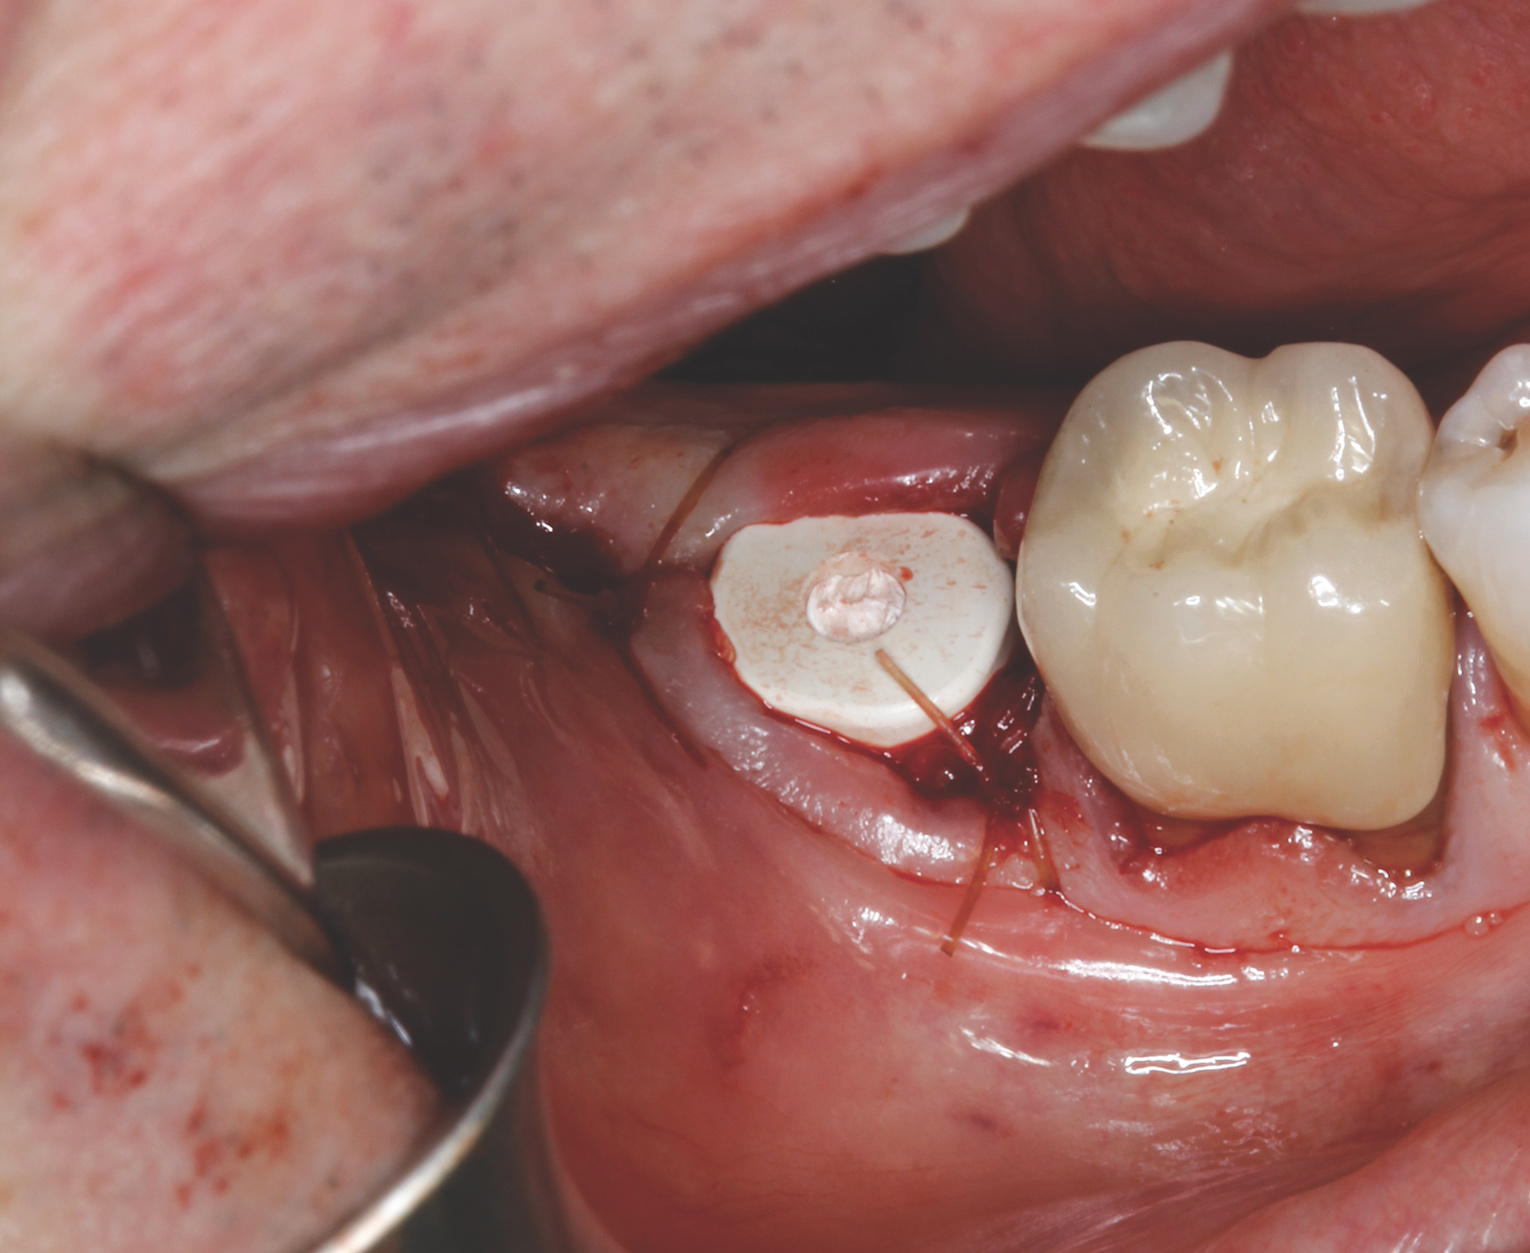

A 68-year-old male patient presented with a failing lower right second molar and retained third molar and was seeking implant restoration at the second molar site (Figure 11 and Figure 12). The patient's medical history was significant for hypertension and cardiac arrhythmia under good control.

After clinical evaluation, CBCT assessment with a dynamic navigation fiducial was followed by planning for immediate implant placement. This included evaluation of inferior alveolar nerve position, undercut, buccal plate dehiscence, implant positioning in the defect, and retention screw path. The patient was taken to surgery under intravenous and local anesthesia with removal of the mandibular right second and third molar teeth. The sites were aggressively debrided with a mesiobuccal root dehiscence noted, and site development followed with the use of dynamic navigation (Figure 13).

Fig 11. Buccal view of mandibular right second molar.

Figure 11

Fig 12. Preoperative CBCT-reconstructed radiograph.

Figure 12